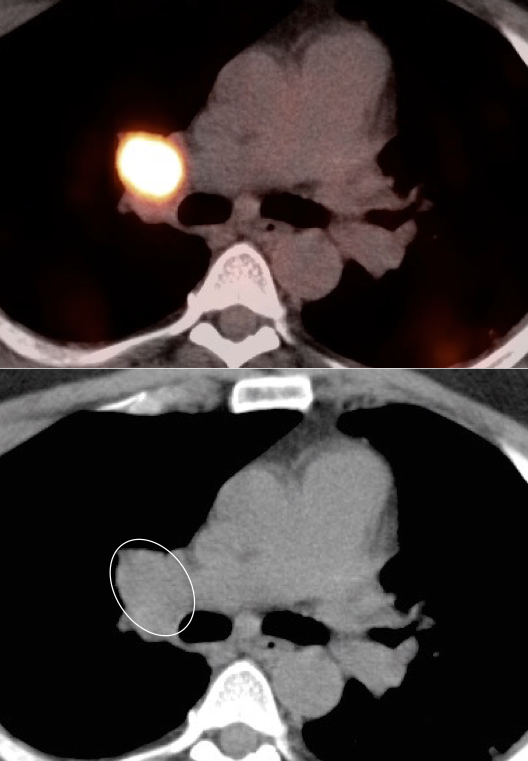

• Hematogenous spread, often to lungs, bone, liver, and brain.

Metastatic Disease: Metastatic RCCA lesions are usually more FDG avid than the primary lesion (nearly all demonstrate metabolic activity greater than liver uptake).

• Can be useful diagnostic tool to assess potential regional or distant metastatic disease.

• PET/CT has high much higher sensitivity for metastatic lesions than for the primary lesion.